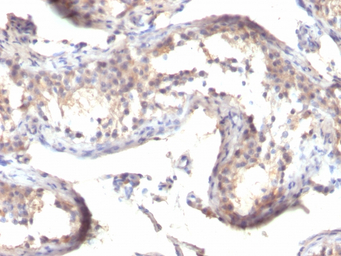

IHC-P analysis of human testicular carcinoma tissue using GTX35107 TGF alpha antibody [TGFA/1119].